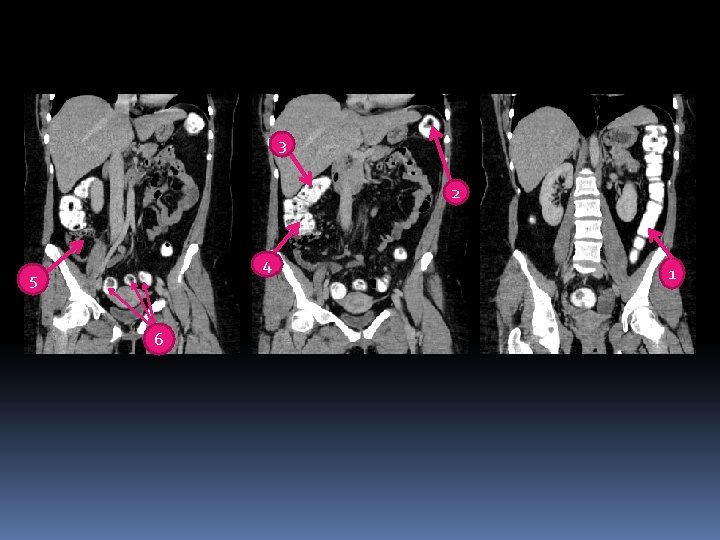

5 2 1 6 4 3

5 2 1 6 1 - Rectum 2 -Sigmoid colon 3 -Descending colon Transverse colon 6 -Cecum 4 3 4 -Ascending colon 5 -

3 2 4 5 6 1

3 2 4 5 1 6 1. 2. 3. 4. 5. 6. Descending colon Splenic flexure Hepatic flexure Ascending colon cecum Sigmoid colon